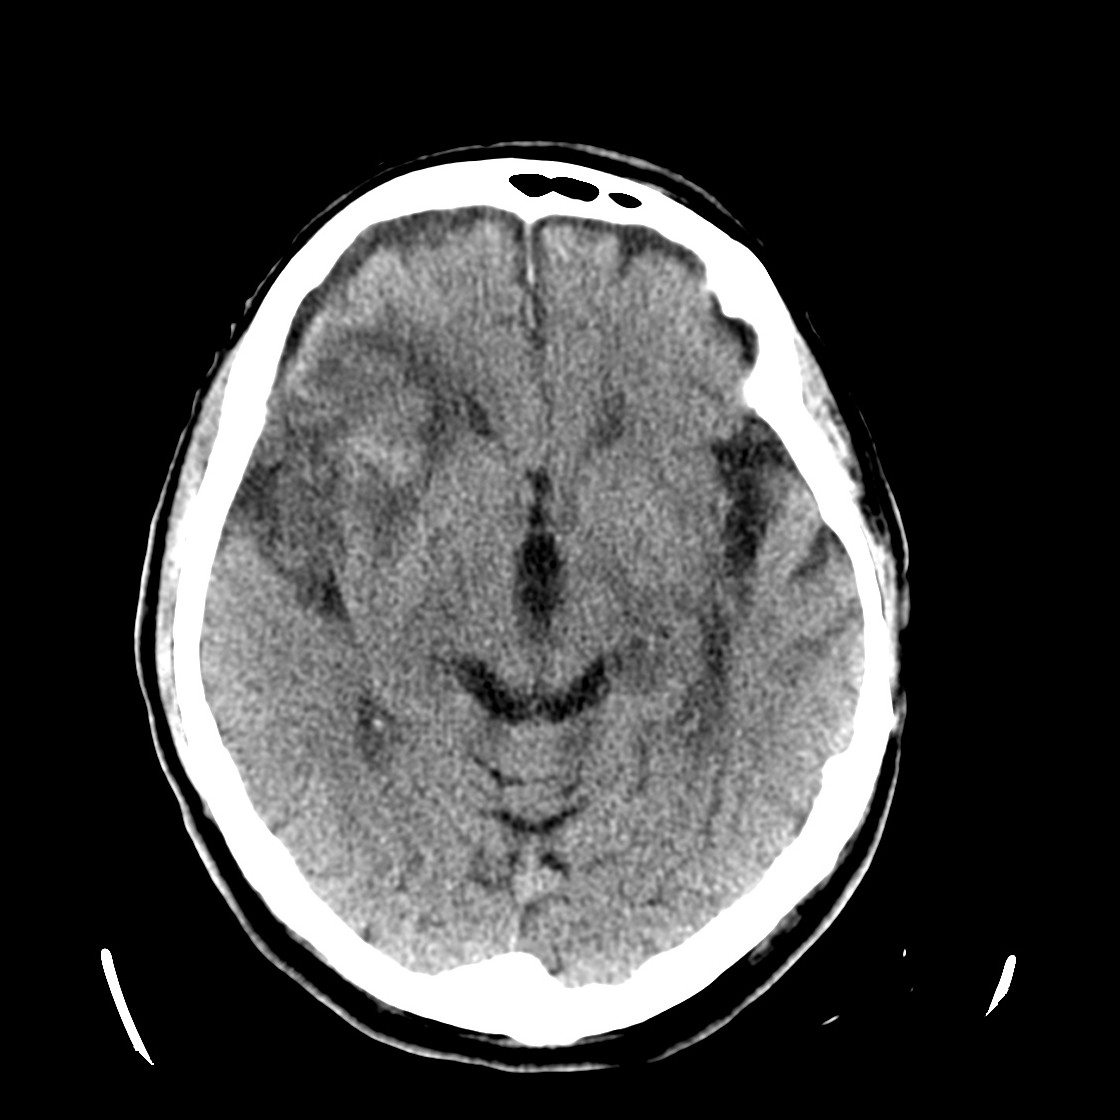

Se realiza un TC de cráneo sin contraste, estos son los hallazgos:

Esta imágen plantea dudas, puede ser una masa o un foco de sangrado, es más, si de esta segunda imagen asumimos que la zona de densidad aumentada corresponde a un sangrado, la pregunta a realizarse ahora es ¿de qué tipo? ¿Es un sangrado intraparenquimatoso, una transformación hemorrágica de un infarto o es otra cosa?

Pues bien, ante los hallazgos descritos, se clarifica que estamos ante un paciente el cual no tiene una masa y que ha sufrido una lesión isquémica hace diez días. Ahora, sobre dicha lesión, tenemos una imagen con un aumento de densidad que sugiere sangrado por una parte y otra hipodensidad en la perifería que correspondería a un edema. Por tanto, descartamos un sangrado intraparenquimatoso de novo. El paciente tiene más de 65 años, no es hipertenso, la imagen del sangrado no es de alta densidad, lo que se opone a una fase aguda o hiperaguda, y tenemos el TC de cráneo previo donde ya se advertía un proceso de tipo isquémico. Por tanto, nos quedan dos opciones, o estamos ante un resangrado de un ACV o estamos ante una Perfusión de lujo.